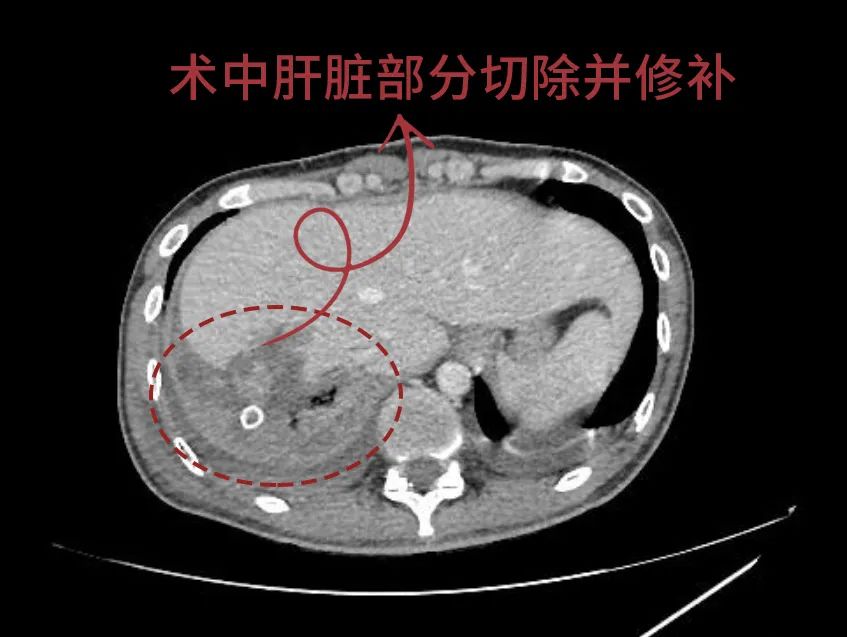

“患者创伤大、受损部位多,每一秒都在失血,且已严重休克,情况危急、刻不容缓、立即手术......”全面评估患者的病情,并经过多学科讨论后,肝胆胰外科专家张宏宇教授果断下达紧急手术指令,一场与死神竞速的“生命保卫战”迅速展开。